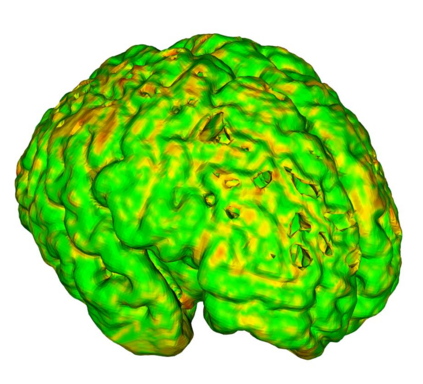

Fetal cortical plate segmentation is essential in quantitative analysis of fetal brain maturation and cortical folding. Manual segmentation of the cortical plate, or manual refinement of automatic segmentations is tedious and time-consuming. Automatic segmentation of the cortical plate, on the other hand, is challenged by the relatively low resolution of the reconstructed fetal brain MRI scans compared to the thin structure of the cortical plate, partial voluming, and the wide range of variations in the morphology of the cortical plate as the brain matures during gestation. To reduce the burden of manual refinement of segmentations, we have developed a new and powerful deep learning segmentation method. Our method exploits new deep attentive modules with mixed kernel convolutions within a fully convolutional neural network architecture that utilizes deep supervision and residual connections. We evaluated our method quantitatively based on several performance measures and expert evaluations. Results show that our method outperforms several state-of-the-art deep models for segmentation, as well as a state-of-the-art multi-atlas segmentation technique. We achieved average Dice similarity coefficient of 0.87, average Hausdorff distance of 0.96 mm, and average symmetric surface difference of 0.28 mm on reconstructed fetal brain MRI scans of fetuses scanned in the gestational age range of 16 to 39 weeks. With a computation time of less than 1 minute per fetal brain, our method can facilitate and accelerate large-scale studies on normal and altered fetal brain cortical maturation and folding.